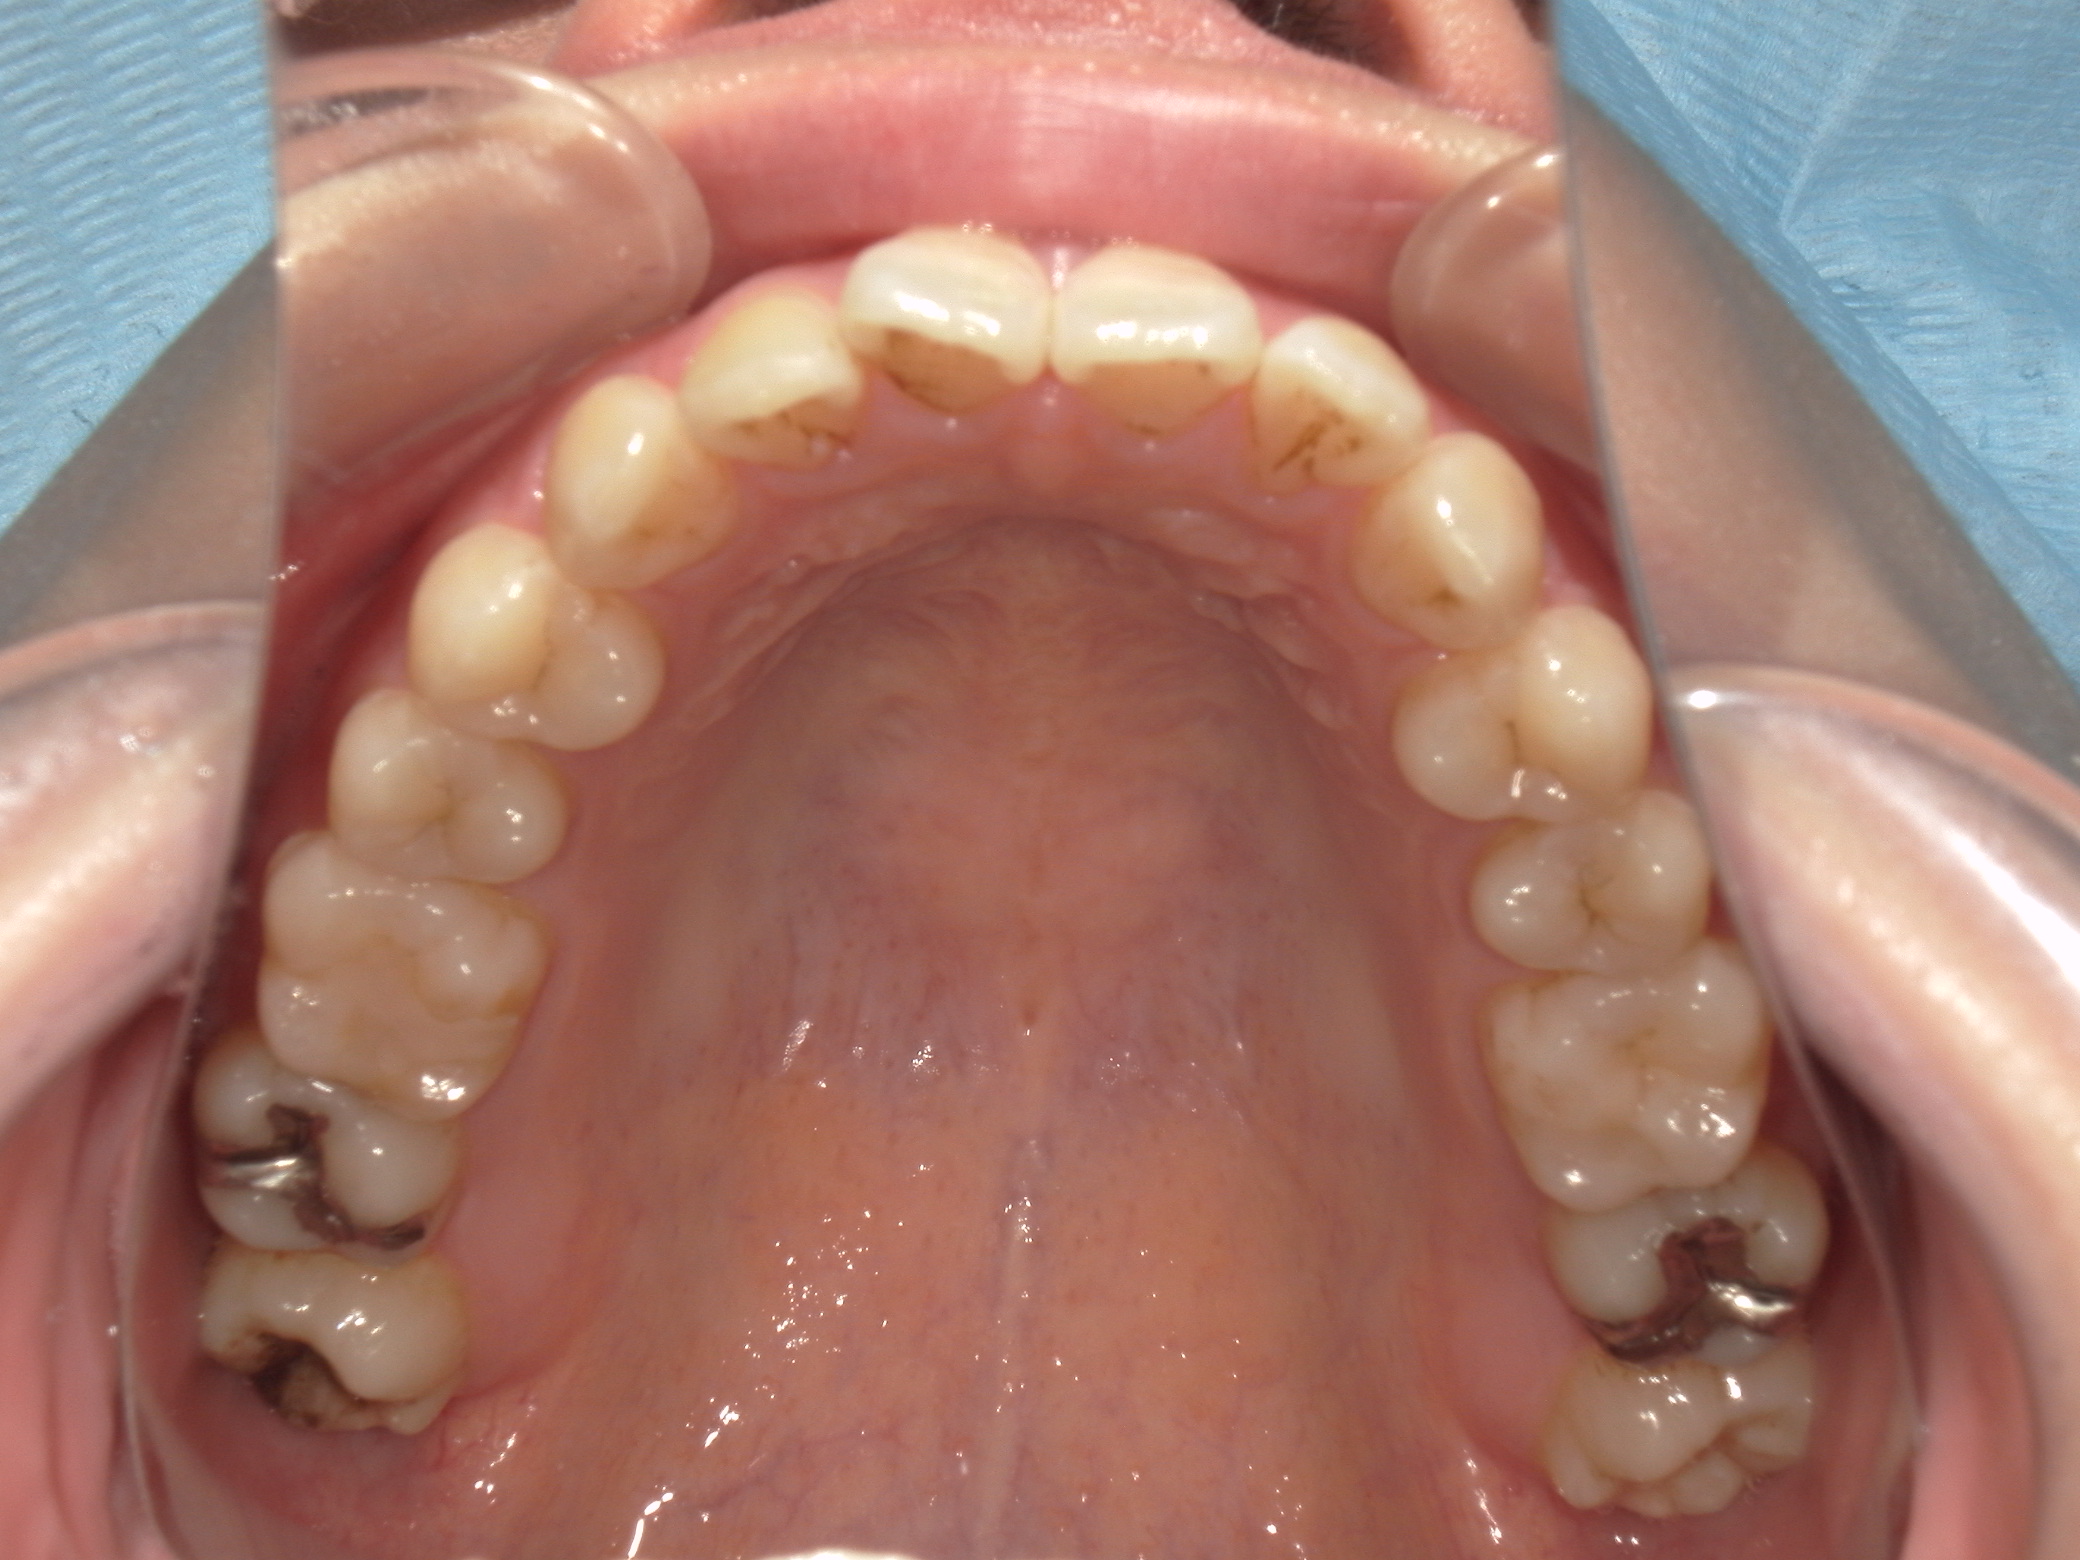

口元の突出を主訴に来院。

上下小臼歯抜歯により突出感を改善する計画を立てた。確立した咬合を崩さないように治療を進める事を目標とした。

患者はハーフリンガル矯正を希望した。

治療後、口元の突出感の改善、咬合関係は維持することができた。